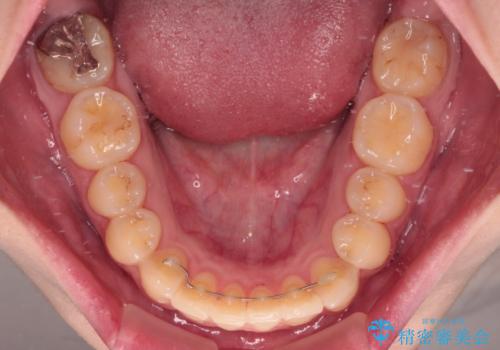

舌側転位している側切歯特有の、切縁の位置が不揃いであったり、根元が内側に引っ込んだ状態であったりという、インビザライン独特の仕上がりになることなく、きれいに整った歯列とすることができました。

インビザライン単体でも治療は可能ですが、安全策としてインビザラインで歯列を移動する前に上顎前歯をワイヤー矯正で整え、その後上下歯列をインビザラインにて矯正治療を行うこととしました。